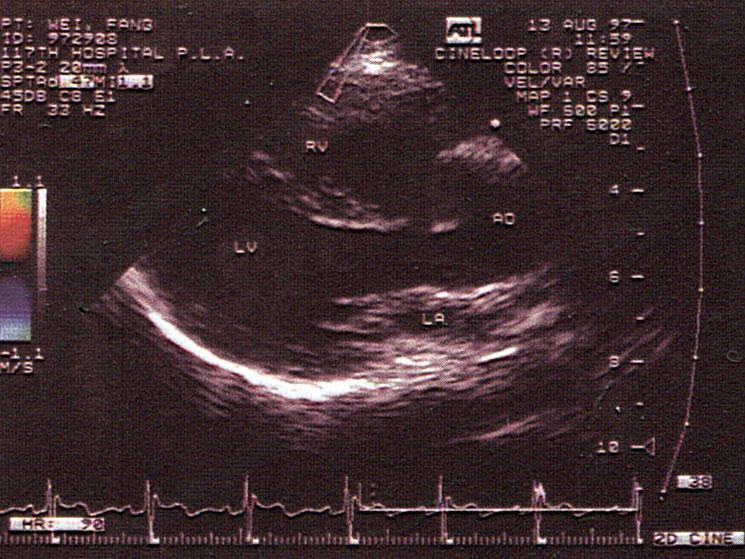

该切面未显示法洛四联症哪一症?(?)A.主动脉骑跨B.室间隔缺损C.肺动脉狭窄D.右室肥厚E.左心缩小

问题 该切面未显示法洛四联症哪一症?(?)

选项 A.主动脉骑跨 B.室间隔缺损 C.肺动脉狭窄 D.右室肥厚 E.左心缩小

答案 C